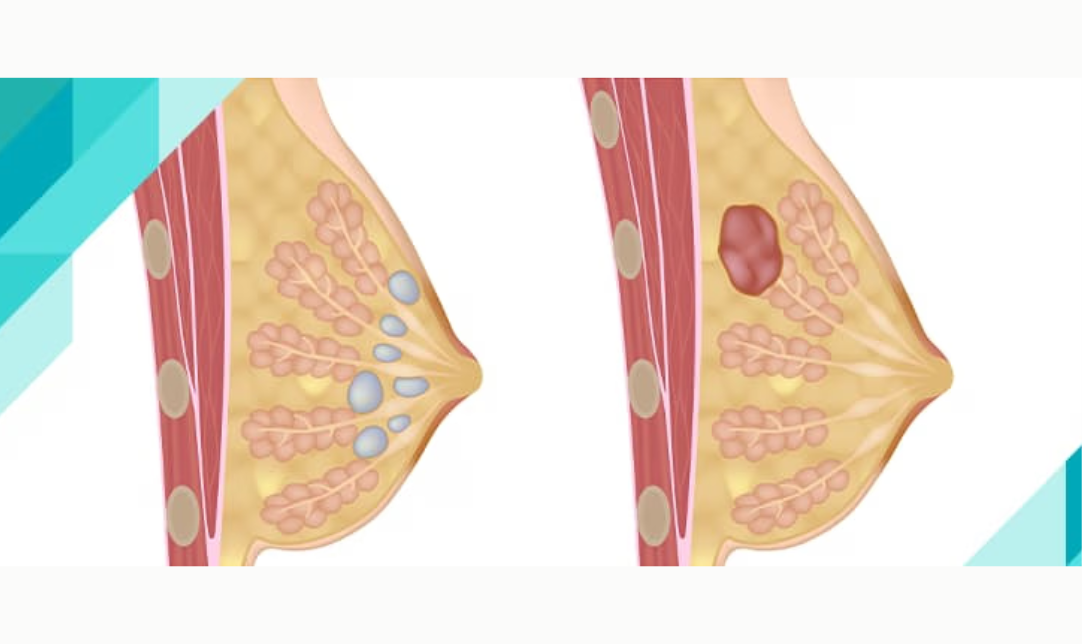

4. Fibroadenoma

Fibroadenoma adalah benjolan jinak di jaringan payudara yang umum terjadi pada wanita muda.

Ciri-ciri: Benjolan kenyal, bergerak, dan tidak nyeri.

Pemeriksaan: Biasanya menggunakan USG atau mammografi untuk memastikan benjolan jinak.

Penanganan: Pemantauan rutin atau operasi jika membesar atau mengganggu.